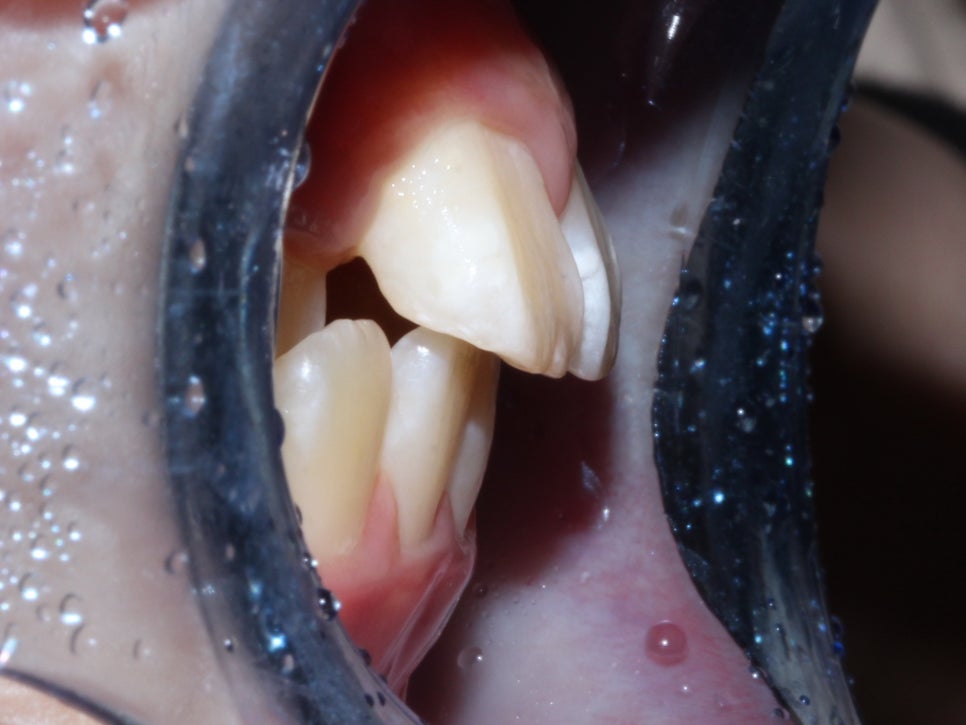

환자분의 상태를 살펴보면

치아가 날 공간이 부족하거나 치아가 나오는 방향에서

앞니가 앞으로 나오고 다른 치아가 기울어지면서

거꾸로 물리는 현상이 발생한 걸로 보여요.

안 모의 변화 모습이에요.

상/하악 전치 모두 상당량이 후방으로 이동이 되었기

때문에 훨씬 심미적으로 변화가 되었어요.